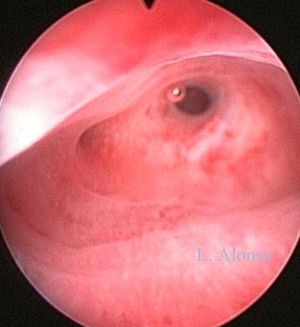

Hysteroscopy

The most common predisposing factors to intrauterine adhesions seems to be curettage of a pregnant or recently pregnant uterus